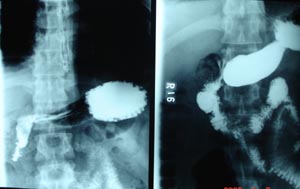

Normal barium swallow

Each part of the stomach & duodenum should be checked to ensure that no abnormal narrowing is present. A transient contraction wave must not be confused with a constant pathological narrowing.